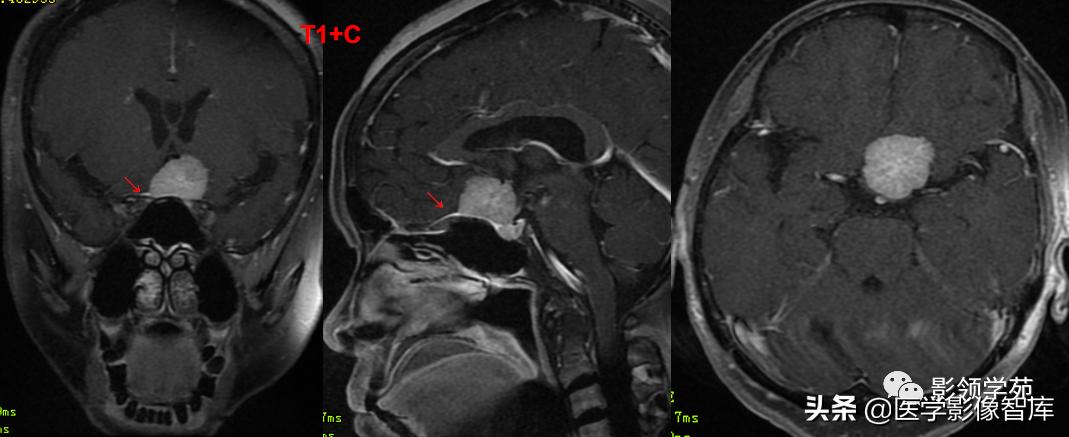

女 61岁 反复头晕3年余

鞍上可见一类圆形均匀稍高密度灶,CT值约47HU,

边界清楚,其内见一小点片状钙化灶;继发鞍上池受压伴变性。

鞍区占位肿块,呈等T1等T2信号,信号均匀,边界清楚。

病灶呈均匀、显著强化(馒头样),以宽基底与前颅窝底相连,

冠状位和矢状位见脑(硬)膜尾征;

肿块突入鞍上池,向上推压视交叉,后缘紧邻垂体柄,与双侧颈内动脉相邻。

(脑膜尾征:增强扫描,肿块邻近的增厚硬脑膜呈窄带状强化,随着远离肿瘤

而逐渐变细。)